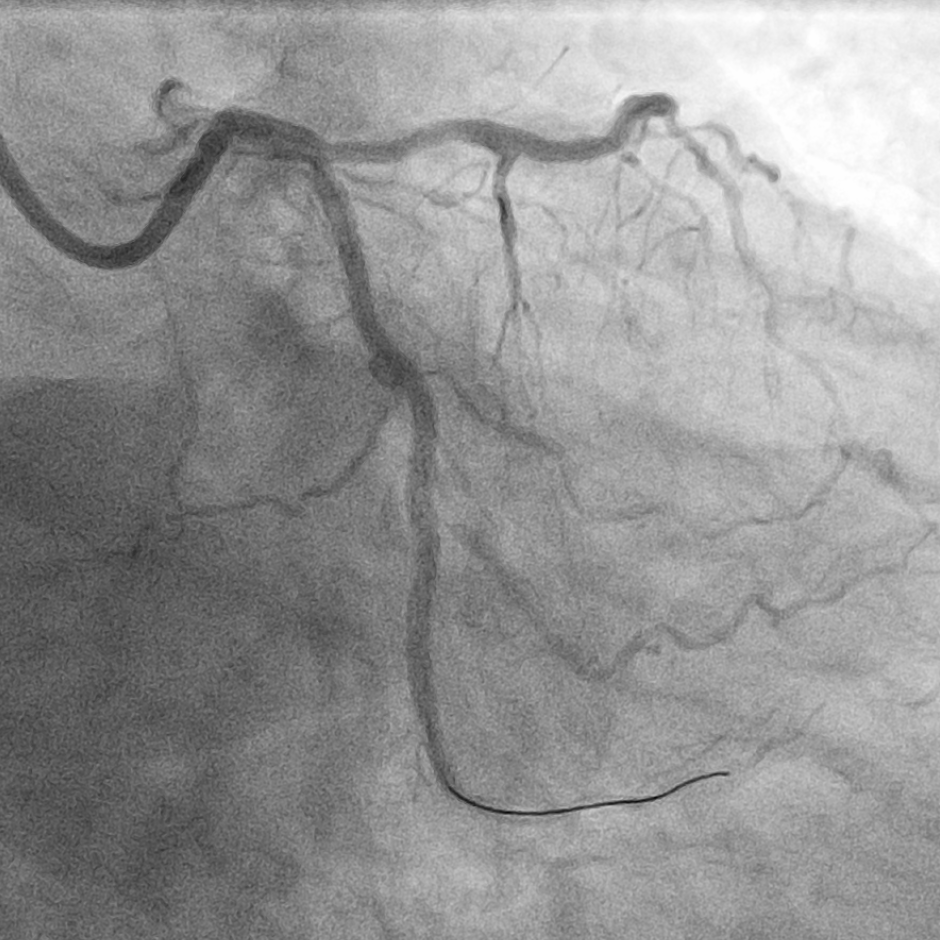

患者为一位72岁老年男性,既往有冠心病 PCI术病史2年,有“高血压病、2型糖尿病”病史10余年,此次因劳力性心绞痛症状入院,复查冠脉造影显示,左回旋支中远端可见约80-90%弥漫性重度狭窄,血管迂曲且合并有严重钙化,使用QFR评估此靶血管为0.45,需要进一步介入干预。

LCX造影提示近远段狭窄、钙化严重

术中IVUS检查提示患者左回旋支近远段多处偏心钙化及钙化小结,钙化较重,导致多种介入器械难以通过,因此启动Shockwave冲击波球囊技术方案。